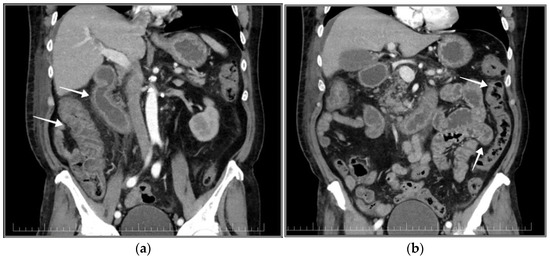

2.2. Physical Examination, Blood Tests, Ultrasound and CT Scan